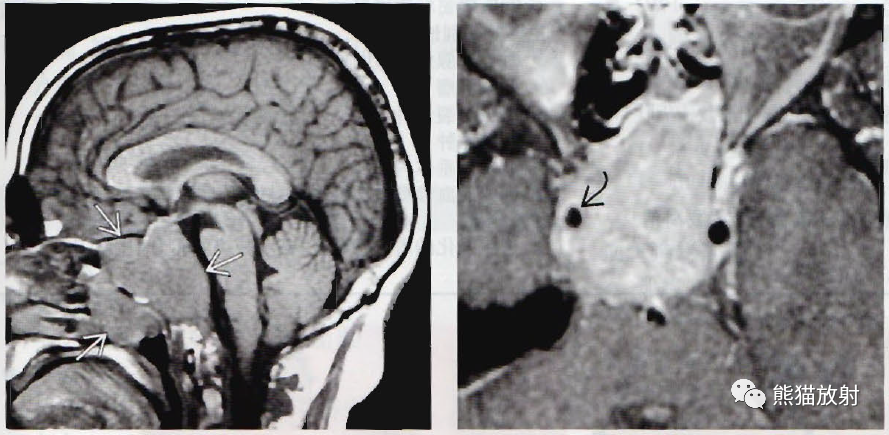

(左)冠状位图显示小的微腺瘤(箭)使右侧垂体轻度扩大,漏斗左移。

(右)冠状位显微病理学显示正常垂体包绕一小的无功能微腺瘤,为尸检偶然发现。

(左) 冠状位T1WI C+MR显示轻度扩大的垂体内有一强化稍弱的病灶。患者无症状,该病灶为偶然发现。垂体“偶发瘤”常见(见于15%~20%的病例) ,可能代表无功能性腺瘤或非肿瘤性囊肿(如中间部囊肿或Rathke裂囊肿) 。

(右) 一例催乳素升高的女性患者,冠状位T1WI MR显示垂体左侧部内一8mm的结节。多数微腺瘤位于侧方。

(左) 冠状位动态T1WI C+MR显示正常垂体强化。因垂体左侧的病灶比正常垂体强化慢,8mm的病变清楚可见。

(右) 动态增强后,冠状位T1WI C+MR显示病灶明显延迟强化。如果结节没有局部增大,在标准T1WI C+扫描上不能辨认。

(左) 一例无症状患者,冠状位CECT显示垂体内小的无强化灶。

(右) 同一患者,矢状位T1WI C+MR显示垂体轻度增大,CT扫描上的小病灶可见,无强化。在对比增强CT和MR扫描中,垂体“偶发瘤”常见。